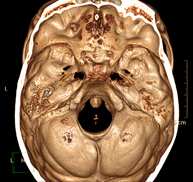

- TC Cráneo

Prueba radiológica que consiste en obtener imágenes del cráneo de alta definición anatómica (tronco cerebral, cerebelo, cerebro, calota craneal, etc.), mediante el empleo de un equipo de TC (Tomografía Computarizada).Indicaciones: traumatismos, cefalea, trastornos de la memoria, pérdida de fuerza súbita en una extremidad o mitad del cuerpo. - TC Cuello

Prueba radiológica que consiste en obtener imágenes del cráneo de alta definición anatómica mediante el empleo de un equipo de TC (Tomografía Computarizada). Indicaciones: cefalea, estudio de tumores, traumatismo craneal. - TC Cuello